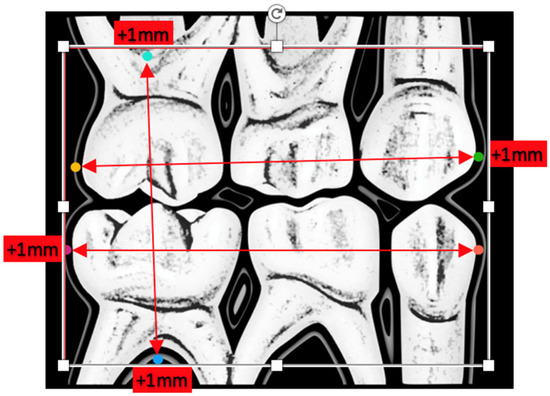

- Anatomical dimensions of the following teeth 55, 54, 53, 63, 64, 65, 75, 74, 73, 83, 84, and 85, as shown in Figure 1. The measurements of the radiographic variables were carried out in duplicate, thus calculating the intraclass correlation coefficient between both measurements to evaluate the intraobserver reproducibility (phase I);